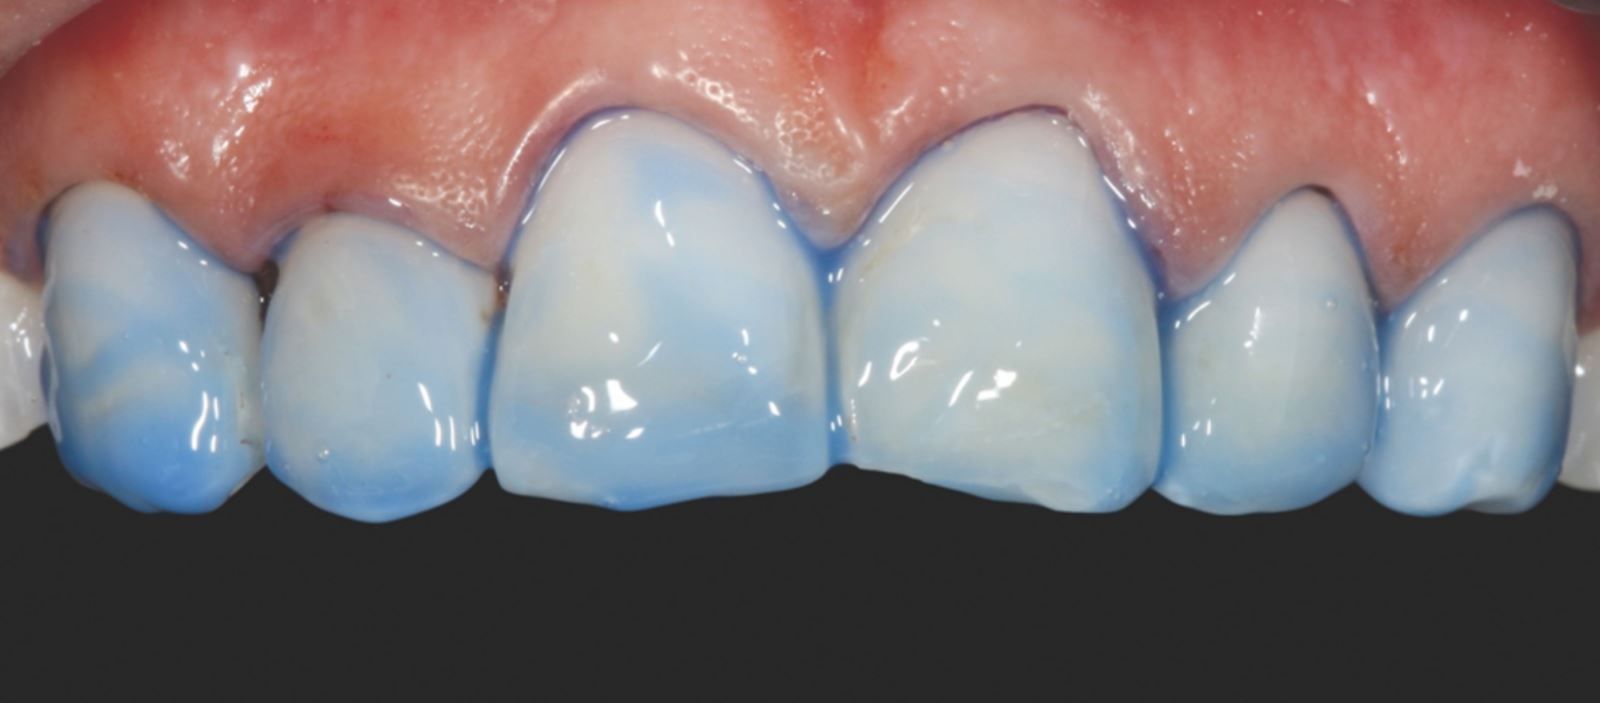

Nepreparovaná sklovina byla leptána 35% kyselinou fosforečnou Ultra-Etch po dobu 30 sekund.

Aplikace a ztenčení adheziva:

Adhezivum Peak Universal Bond bylo aplikováno a ztenčeno vzduchem se současným odsáváním.

Cementace:

Fazety byly cementovány pomocí pryskyřičného cementu PermaShade™ LC v odstínu Translucent (není dostupný v Evropě).

Výsledek cementace:

Finální cementace vedla ke stabilnímu a esteticky přijatelnému uložení fazet.

Modelace anatomie fazet

K modelaci anatomie fazet byly použita diamantová brouska ve tvaru míče na ragby a dlouhý tenký diamantový brousek. K vytvoření linií Retzia (SR lines) byla použita lobulární diamantový brousek (segmentovaný, „laločnatý“ tvar). Počáteční leštění proběhlo s Jiffy™ Natural, finální lesk byl dosažen přípravkem Ultradent™ Diamond Polish Mint a Jiffy™ Goat Hair Brush (není dostupný v Evropě), aby nedošlo k odstranění terciární anatomie.

Výsledek a závěrečné zhodnocení

Tento postup úspěšně vyřešil estetické obavy pacientky překrytím diskolorace horních frontálních zubů a dosažením přirozeného, vyváženého vzhledu ve vztahu k dolním frontám. Použití kompozitních fazet bez preparace poskytlo konzervativní, vysoce efektivní řešení, které respektovalo finanční možnosti pacientky a její požadavek na minimálně invazivní přístup.